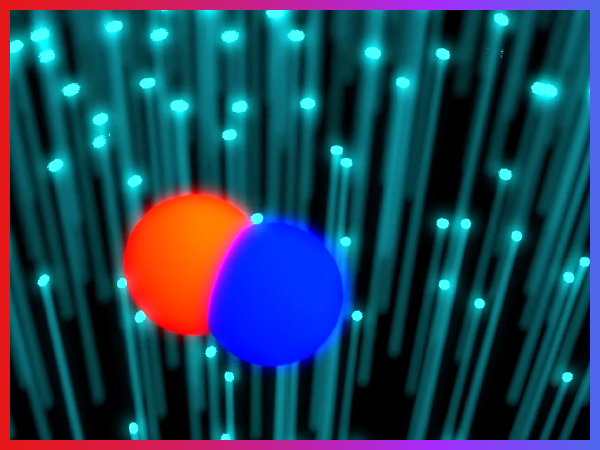

视频摘要范例展示

Impact of cell-free hemoglobin on contracting skeletal muscle microvascular oxygen pressure dynamics